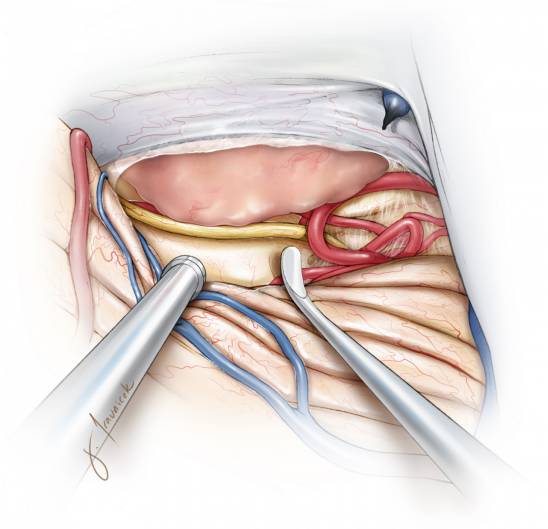

图7. 识别天幕游离缘旁的滑车神经。将位于天幕缘旁的滑车神经及周围血管结构充分游离并保护起来,如果可行,先将这部分肿瘤减容。天幕游离缘附近的脑干背外侧神经神经血管结构要在大规模切除肿瘤之前充分暴露,以免切除过程中由于视野不清误伤。

像上图所示的方式靠近肿瘤并切开天幕将会有助于减少肿瘤血供,并提供一个相对无血的区域来切除和分离肿瘤。

图12. 在对肿瘤进行足够的内减压后,再分离瘤壁与周围如枕叶底部和颞叶后部等神经血管组织,在这分离过程中注意保护大脑后动脉。